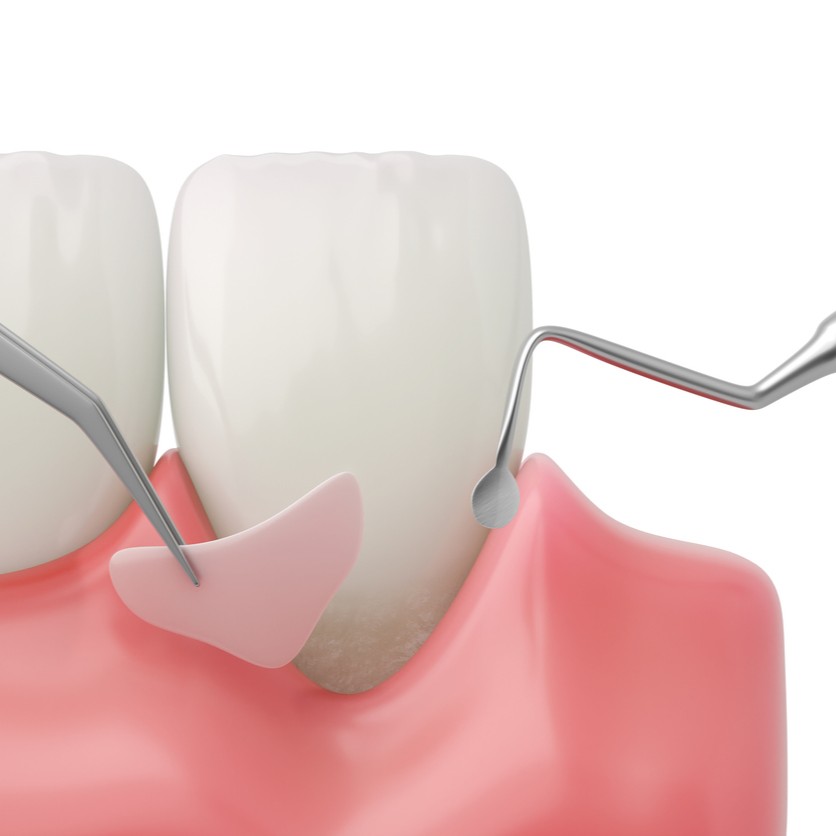

Détartrage et surfaçage radiculaire

La première étape du traitement parodontal repose sur le détartrage professionnel, qui élimine la plaque et le tartre au-dessus et en dessous de la gencive. En cas d’atteinte plus avancée, un surfaçage radiculaire est nécessaire : il consiste à nettoyer en profondeur les racines des dents pour éliminer les bactéries et lisser la surface radiculaire. Ces traitements permettent de réduire l’inflammation, de favoriser la cicatrisation des gencives et de stabiliser l’évolution de la maladie.